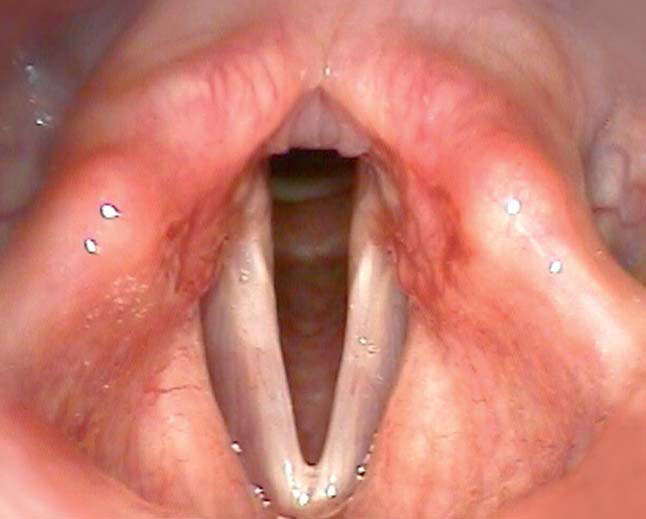

Для диагностики дисфонии и других нарушений деятельности голосового аппарата рутинным стал метод эндоскопической стробоскопии. Стробоскопический метод основан на зрительной иллюзии неподвижности объекта в мерцающем с частотой движения объекта свете и позволяет оценить различные фазы движения голосовых складок. Метод эффективен в диагностике нарушений голоса, связанных с анатомическими причинами. Недостатком метода является недостаточная диагностическая ценность исследования в случае наличия нерегулярных движений голосовых складок.

В то время как стробоскопический метод позволяет проанализировать 25 кадров в секунду, предлагаемый компанией производителем метод высокоскоростной фотографии позволяет получить до 4000 кадров высокого разрешения в секунду. Таким образом, метод высокоскоростной фотографии имеет значительные преимущества перед стробоскопическим методом во многих клинических ситуациях, позволяет оценить индивидуальные отклонения в движении голосовых складок прецизионно, увидеть начальную и завершающую фазы движения складки, которая не сопровождается фонацией. Кроме того, цветное изображение позволяет оценить не только функциональную, но и морфологическую структуру.

Наряду с классическими системами для стробоскопических исследований в фониатрии и общей оториноларингологии, Richard Wolf, наиболее инновационный производитель медицинского оборудования в Германии, представляет высокоскоростную видеокамеру высокого разрешения HreS Endocam 5562.